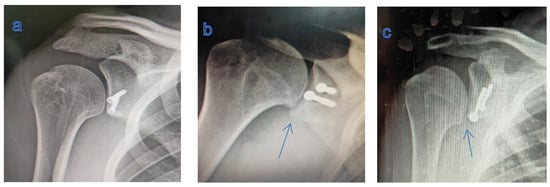

Post-operative GH arthritis was not radiologically detected in 14 patients (66.7%), whereas it was a grade I in 5 patients (23.8%) and a grade II in 2 patients (9.5%), with no progression compared to pre-operative evaluation (Figure 5).

Figure 5. (a) X-ray showing no GH arthritis; (b,c) X-ray showing humeral osteophytes (blue arrows): grade I GH arthritis.